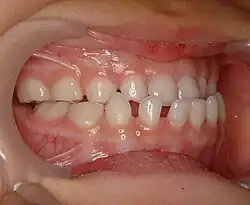

Правильным прикусом принято считать тот прикус, где верхние резцы (incisivi) закрывают собой резцы нижней челюсти, а верхние клыки загораживают нижние; верхние премоляры плотно соприкасаются с нижними, а моляры нижней челюсти находятся чуть ближе к полости рта, чем верхние.

Ортогнатический прикус

Прикус, при котором верхние фронтальные зубы на одну треть длины перекрывают коронки нижних зубов[2].